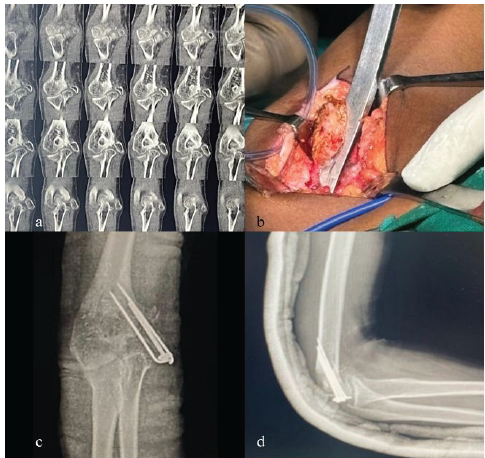

(K-Wire with cannulated cancellous [CC] screw) A 15-year-old male sustained an injury while playing cricket following a fall on his outstretched arm. Examination revealed medial swelling, tenderness, and valgus instability, with radiographs confirming a malunited medial epicondyle fracture. Open reduction was performed via a medial approach. Osteotomy was done using a K-wire for temporary stabilization and a CC screw for definitive fixation. At 12 weeks, radiological union was achieved with elbow range of motion (ROM) of 0–130° and no residual instability (Figs. 1 and 2).

Figure 2: Pre-operative computed tomography (CT) image, intra-operative clinical picture, and post-operative X-rays (a) CT images of right elbow, (b) intra-operative clinical picture of exposure and osteotomy, (c) post-operative X-ray right elbow anterior-posterior view, (d) post-operative X-ray right elbow lateral view.